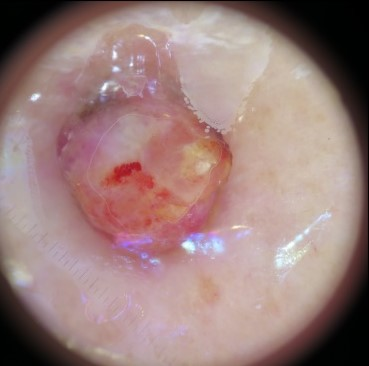

State-of-the-art deep learning approaches for skin lesion recognition often require pretraining on larger and more varied datasets, to overcome the generalization limitations derived from the reduced size of the skin lesion imaging datasets. ImageNet is often used as the pretraining dataset, but its transferring potential is hindered by the domain gap between the source dataset and the target dermatoscopic scenario. In this work, we introduce a novel pretraining approach that sequentially trains a series of Self-Supervised Learning pretext tasks and only requires the unlabeled skin lesion imaging data. We present a simple methodology to establish an ordering that defines a pretext task curriculum. For the multi-class skin lesion classification problem, and ISIC-2019 dataset, we provide experimental evidence showing that: i) a model pretrained by a curriculum of pretext tasks outperforms models pretrained by individual pretext tasks, and ii) a model pretrained by the optimal pretext task curriculum outperforms a model pretrained on ImageNet. We demonstrate that this performance gain is related to the fact that the curriculum of pretext tasks better focuses the attention of the final model on the skin lesion. Beyond performance improvement, this strategy allows for a large reduction in the training time with respect to ImageNet pretraining, which is especially advantageous for network architectures tailored for a specific problem.